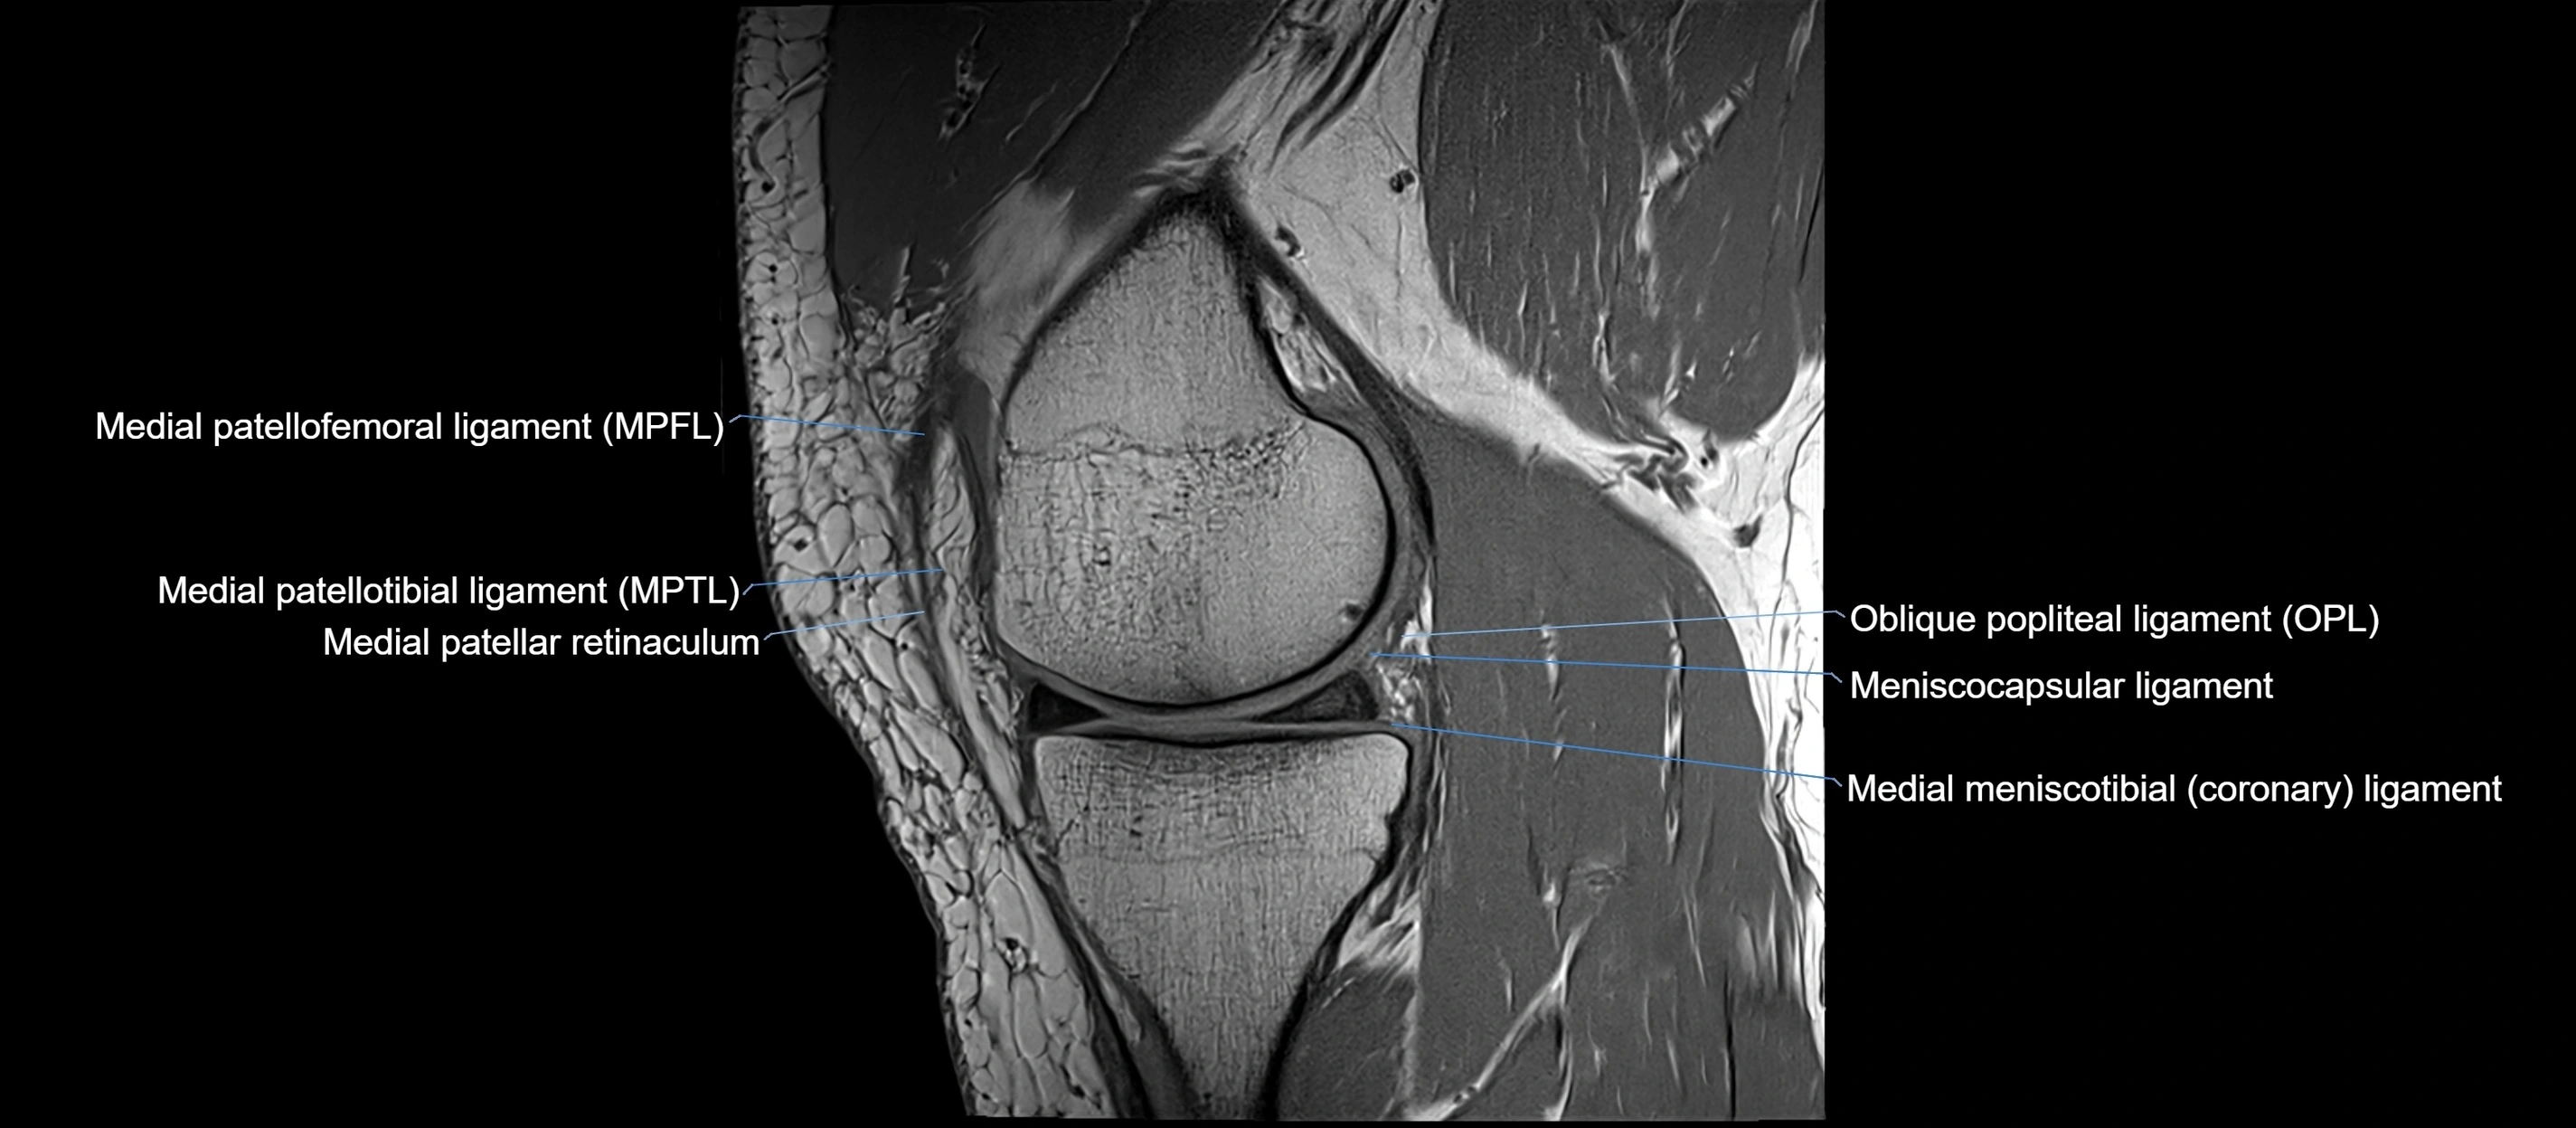

MRI images

image